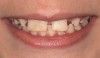

Fig 1 and Fig 2. Pretreatment photographs. Patient at 9 years of age on presentation.

A 9-year-old girl, referred to a prosthodontic office by her pediatric dentist, presented with her mother’s chief complaint: “The kids are teasing her about her big front tooth.” Findings from radiographic and clinical examinations revealed fused maxillary central-peg lateral incisors, teeth Nos. 7 and 8, and a congenitally missing lateral incisor, tooth No. 10 (Figure 1 through Figure 3). An implant was selected as the ideal treatment to replace tooth No. 10 when somatic growth was complete. A diagnostic wax-up was fabricated to determine if the fused tooth could be made to resemble two teeth, using pink composite to give the illusion of an interproximal papilla. The patient was referred for an orthodontic consultation to plan for closure of the diastema between teeth Nos. 8 and 9 and achievement of proper alignment for implant No. 10. The patient was also referred to a periodontist for pretreatment assessment of the tooth No. 10 site. An endodontist was consulted should exposure of the large pulp occur during tooth preparation.